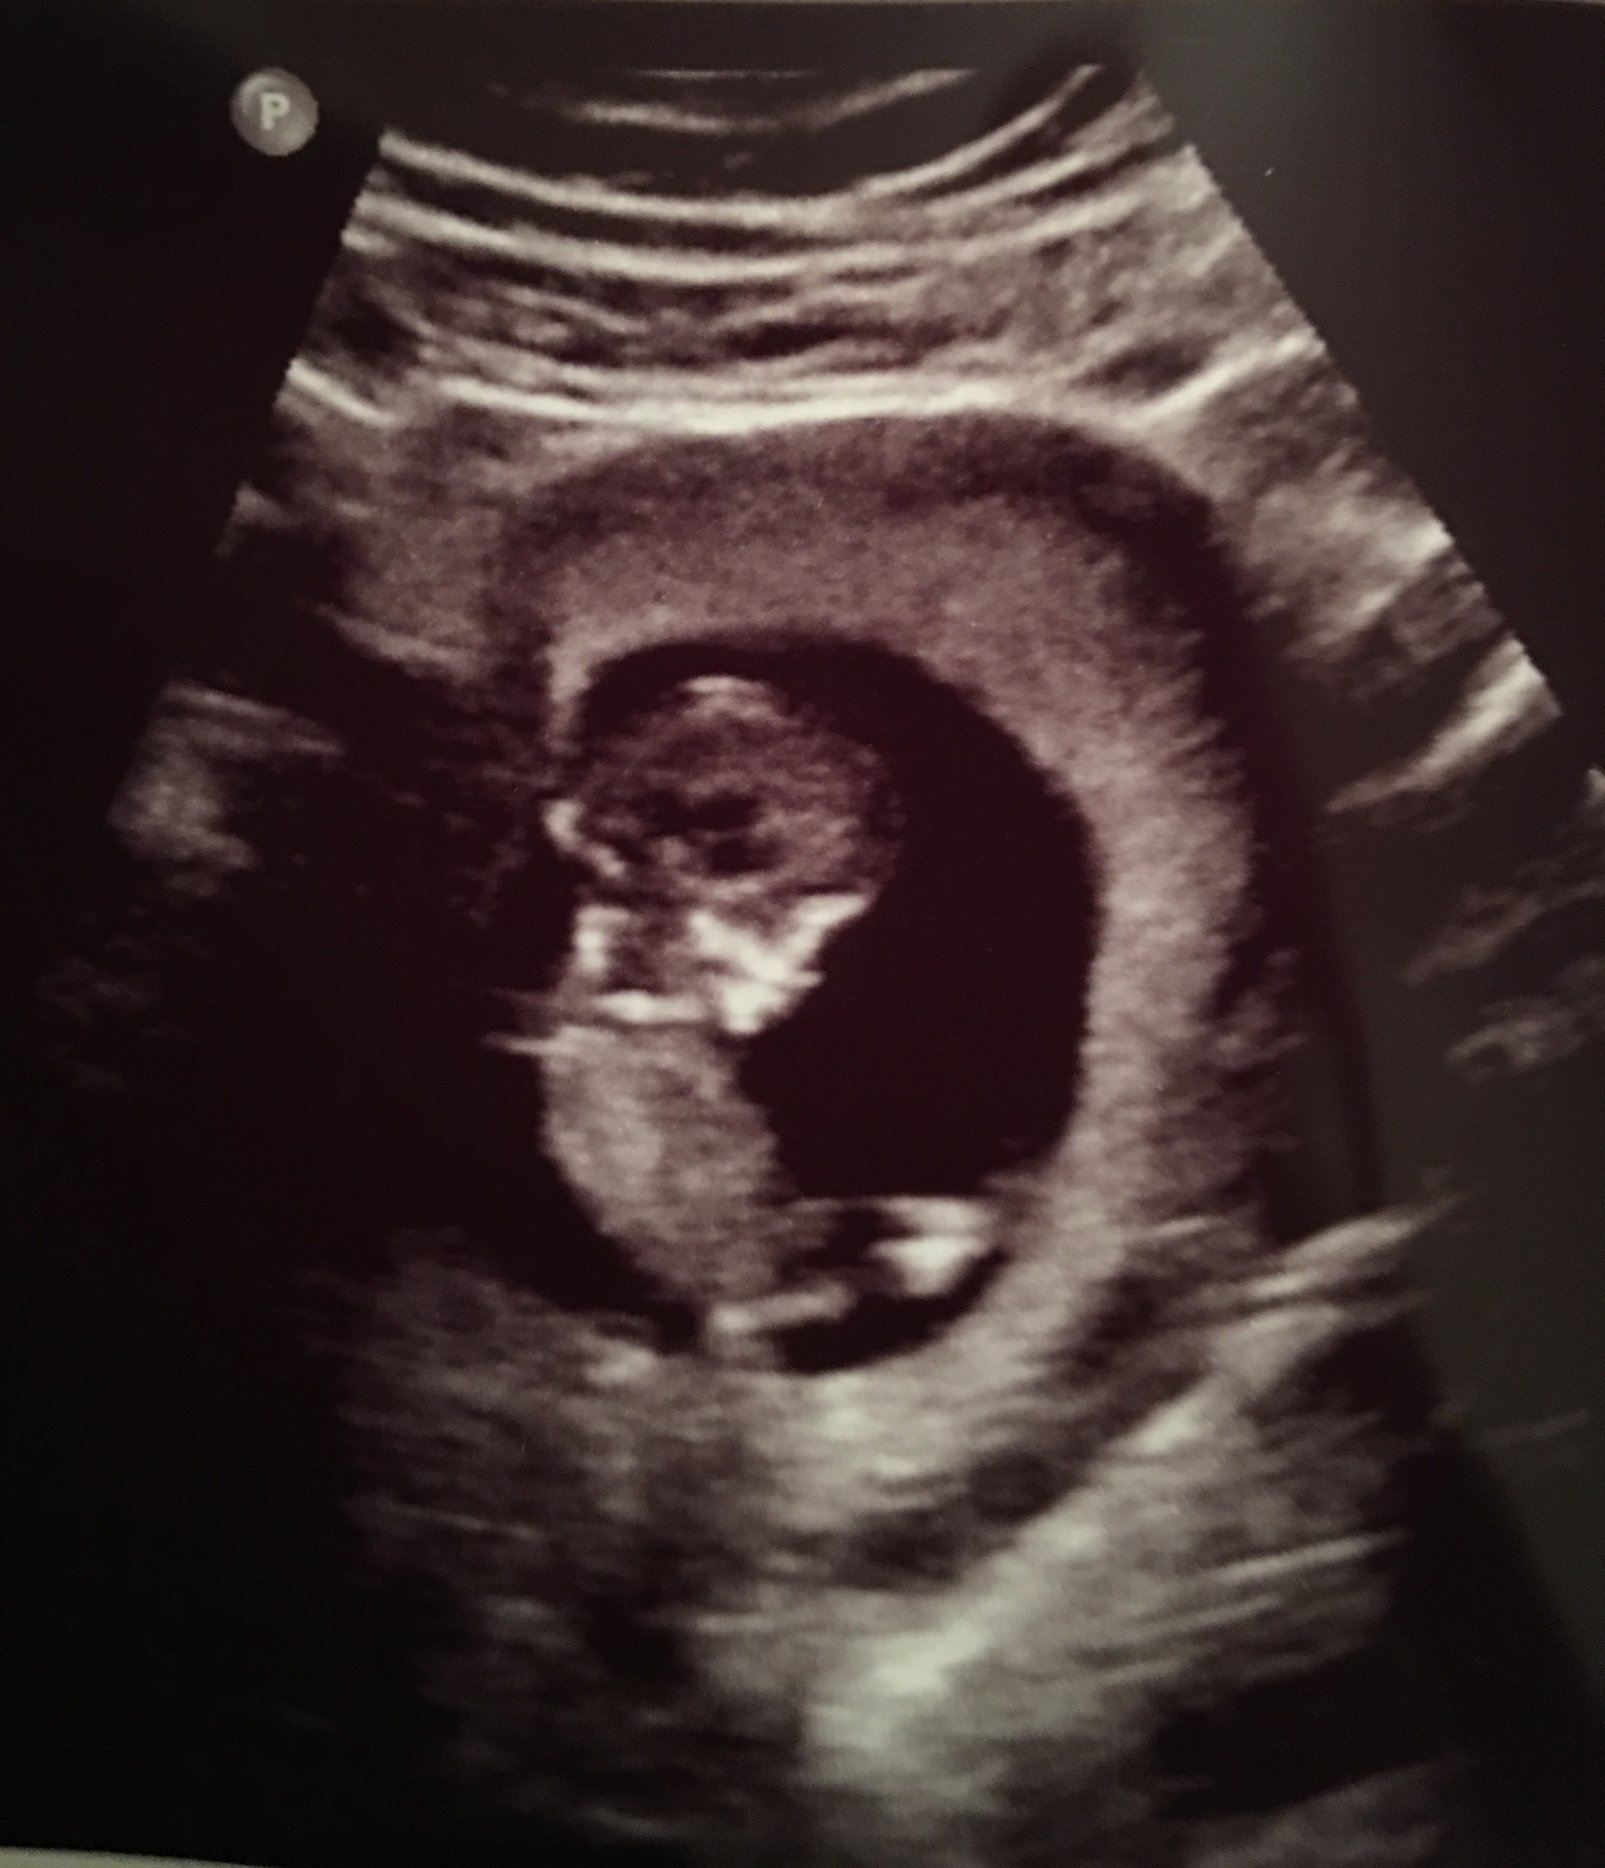

Our little baby!! 12 weeks 4 days and actually looking like a baby now it was so fun getting to watch it move around! This is my first pregnancy and due date is September 3rd!